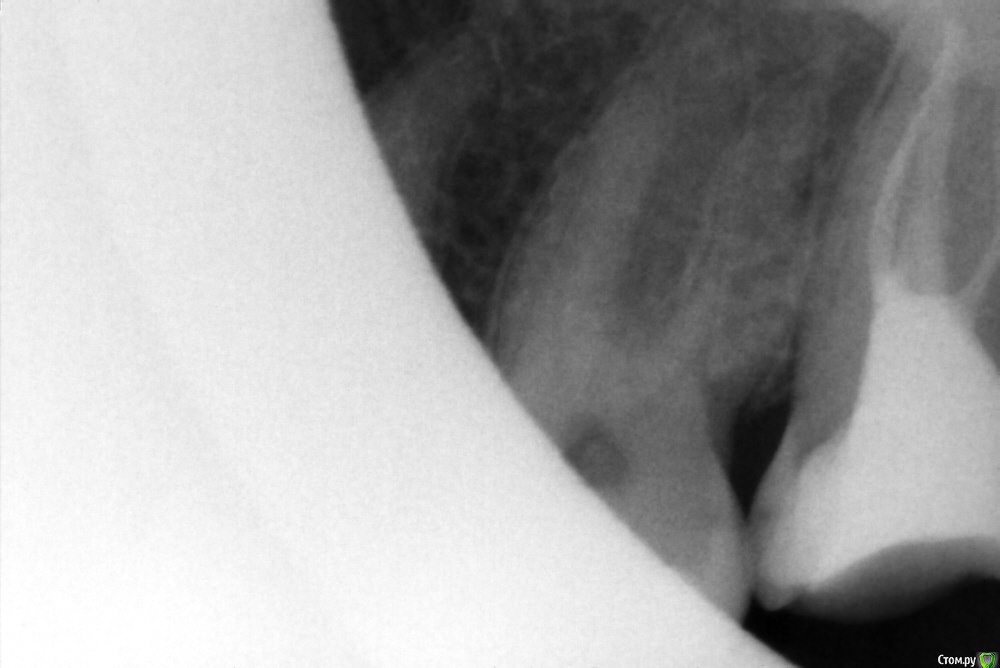

вдгиф Опубликовано 26 января, 2015 Поделиться Опубликовано 26 января, 2015 (изменено) Добрый день, год назад отломился зуб- депульпированный. Не беспокоит. Врач, сделав снимок и узнав, что не беспокоит, отказалась перелечивать и настаивает на том, что зуб не надо трогать. Просто обточить и под коронку- мне мол к ортопеду. Посмотрите, пожалуйста, там еще и инструиент говорят есть. Надо ли доставать? Самой конечно не хочется будить лихо, но надо делать все правильно) Спасибо. Изменено 26 января, 2015 пользователем вдгиф Ссылка на комментарий